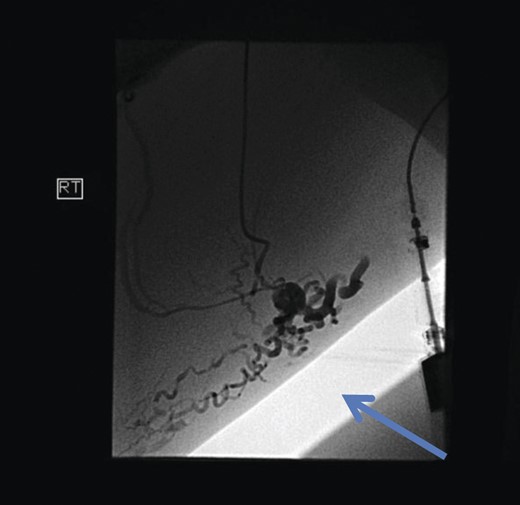

The superficial external pudendal vein was embolized with 1% sodium tetradecyl sulphate and then coiled through a contralateral puncture under fluoroscopic guidance (Figs 3 and 4). The procedure went uneventfully with successful obliteration of the communicating thigh veins to vulval varices (Fig. 5) and the patient was discharged home the same day.

Pre-embolization fluoroscopy showing communication of thigh veins to vulval varices (blue arrow).

Post-procedure fluoroscopy showing successful obliteration of communication of thigh veins to vulval varices (blue arrow).